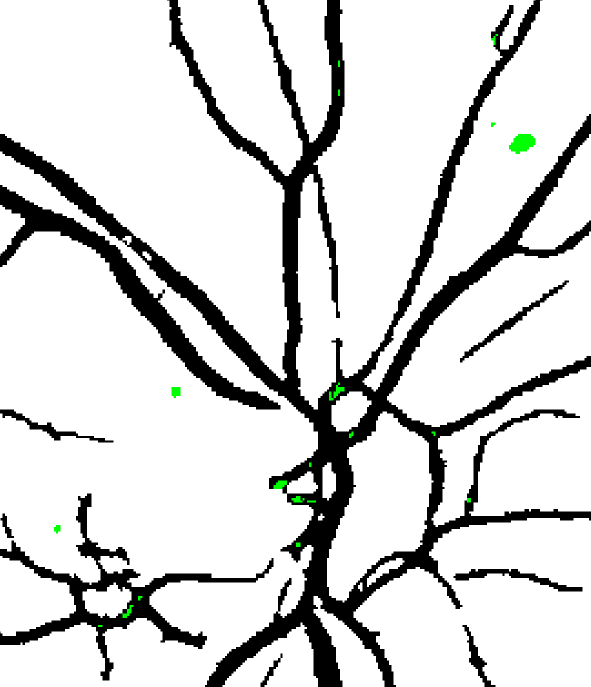

We also analyzed the viability of using the segmentation of the retinal vasculature as a potential source of information. As seen in Figure 5(a), most of the false positive detections are located in vessel crossings or beadings. Thus, we compute an initial vessel segmentation using the method reported in (Orlando and Blaschko, 2014, Orlando et al., 2017a), and postprocessing the output by removing every spurious connected component with less than pixels Orlando et al. (2017b). A morphological closing with a disk of radius 2 is afterwards applied to fill any gap due to the central reflex in arteries. Then, we measure the ratio of pixels in the candidate region that overlap with the segmentation, divided by the number of pixels in the candidate. Figure 6 illustrates the process of computing this feature. It can be seen that most of the false positive lesions located at the optic disc overlap with the resulting segmentation mask, and can be removed by this descriptor.